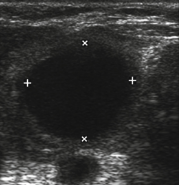

Colloid cyst

A

• Benign

• TIRADS 1

Anechoic cyst containing echogenic foci with comet tail artefact

Avascular

Differential = cystic papillary thyroid cancer